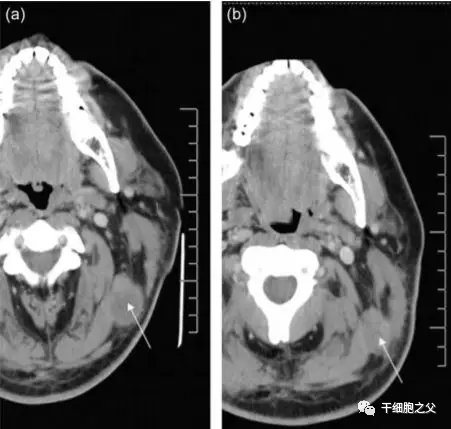

2008年,美国拉什大学医学中心的研究人员将外源扩增的NK异体细胞注入到黑色素瘤患者体内,结果发现,注入注入NK细胞后,该患者左上颈部肿瘤的体积明显降低(从3.15 cm×2.54 cm减小至2.46 cm× 1.76 cm)。同时,该研究也为外源扩增的NK异体细胞是否可以大规模应用于治疗黑色素瘤提供了一定的理论依据。

图片

△ NK细胞治疗前后对比图